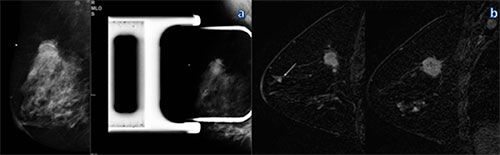

Multi-centric cancer detected at breast MR imaging (MRI) that is occult at mammography appears to represent a larger tumor burden in approximately one-quarter of patients and can upstage the diagnosis, resulting in potential changes in treatment, according to new research published online in Radiology.

Chiara Iacconi, M.D., from the of Breast Unit at USL1 Massa-Carrara in Carrara, Italy, and colleagues reviewed records from 2001 to 2011 that yielded 2,021 patients with newly diagnosed breast cancer who underwent biopsy after preoperative MRI. Of those patients, 285 (14 percent) had additional cancer detected at MRI that was occult at mammography.

In 73 patients (3.6 percent), MRI identified 87 cancers in different quadrants than the known index cancer, constituting the basis of the study. In 62 of 73 patients (85 percent; 95 percent confidence interval [CI]: 75, 92), one additional cancer was found, and in 11 of 73 (15 percent; 95 percent CI: 8, 25), multiple additional cancers were found. A x2 test with adjustment for multiple lesions was used to examine whether MR imaging and pathologic features differ between the index lesion and additional multi-centric lesions seen only at MRI.

Researchers found known index cancers were more likely to be invasive than MRI-detected multi-centric cancers (88 percent vs. 76 percent, P = .023). Ductal carcinoma in situ (21 of 87 lesions [24 percent]; 95 percent CI: 15, 36) represented a minority of additional MRI–detected multi-centric cancers. Overall, the size of MRI-detected multicentric invasive cancers (median, 0.6 cm; range, 0.1-6.3 cm) was smaller than that of the index cancer (median, 1.2 cm; range, 0.05–7.0 cm; P = .023), although 17 of 73 (23 percent) (95 percent CI: 14, 35) patients had larger MRI–detected multi-centric cancers than the known index lesion, and 18 of 73 (25 percent) (95 percent CI: 15, 36) had MRI–detected multi-centric cancers larger than 1 cm.